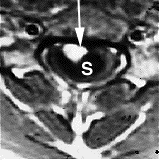

MRI image shows spinal bleeding (myelomalacia). |

There are two tests that can provide a definite diagnosis of myelomalacia; magnetic resonance imaging (MRI), or myelography.[8] Diffuse hyperintensity on T2-weighted imaging, and hypointensity on T1-weighted imaging of the spinal cord can be an indication of the onset or progression of myelomalacia